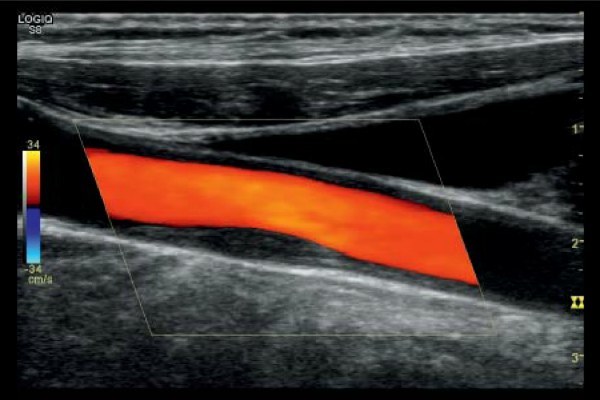

Проводится на цифровой аппаратуре, позволяет получать изображение сосудов, оценивать скорость и направление кровотока в них. Этот метод сочетает серый режим обычного УЗИ с цветовым допплером. Он является очень информативным, точным, доступным для пациента и используется в настоящее время чаще всего.

Ультразвуковое дуплексное сканирование

Этот вариант УЗИ имеет две составляющие – классическая допплерометрия и в дуплексном режиме с цветовым картированием. Кроме определения структуры сосуда, скорости кровотока, УЗДС вен нижних конечностей позволяет определить направление потоков крови, которые под действием ультразвука получают разное цветовое окрашивание.

Показатели, полученные при допплерографии сосудов нижних конечностей, дополняются оценкой состояния стенок вен и артерий, указывают на наличие и размещение тромбов.

С помощью дуплексного сканирования сосудов нижних конечностей врач-сонолог получает более полную информацию о состоянии вены, чем при допплеровском.